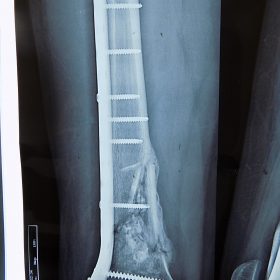

Κατάγματα Μηριαίου ή Κνήμης

Τα κατάγματα της Διάφυσης των οστών της κνήμης και του Μηριαίου οστού στη σύγχρονη ΟΡΘΡΟΠΑΙΔΙΚΗ αντιμετωπίζονται με ΕΝΔΟΜΥΕΛΙΚΗ ΗΛΩΣΗ.

Δύο τομές 3 εκατοστών και 1 εκατοστού αντιστοίχως για την εισαγωγή και το κλείδωμα του ήλου μέσα στο οστό. Η μέθοδος είναι κλειστή,σχεδόν αναίμακτη,διάρκειας 60 λεπτών,με τη βοήθεια C-ARM (τηλεόρασης).